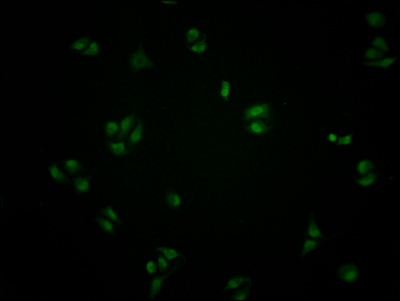

Immunofluorescence staining of Hela cells with CSB-PA002277LA01HU at 1:100, counter-stained with DAPI. The cells were fixed in 4% formaldehyde and blocked in 10% normal Goat Serum. The cells were then incubated with the antibody overnight at 4°C. The secondary antibody was Alexa Fluor 488-congugated AffiniPure Goat Anti-Rabbit IgG(H+L).